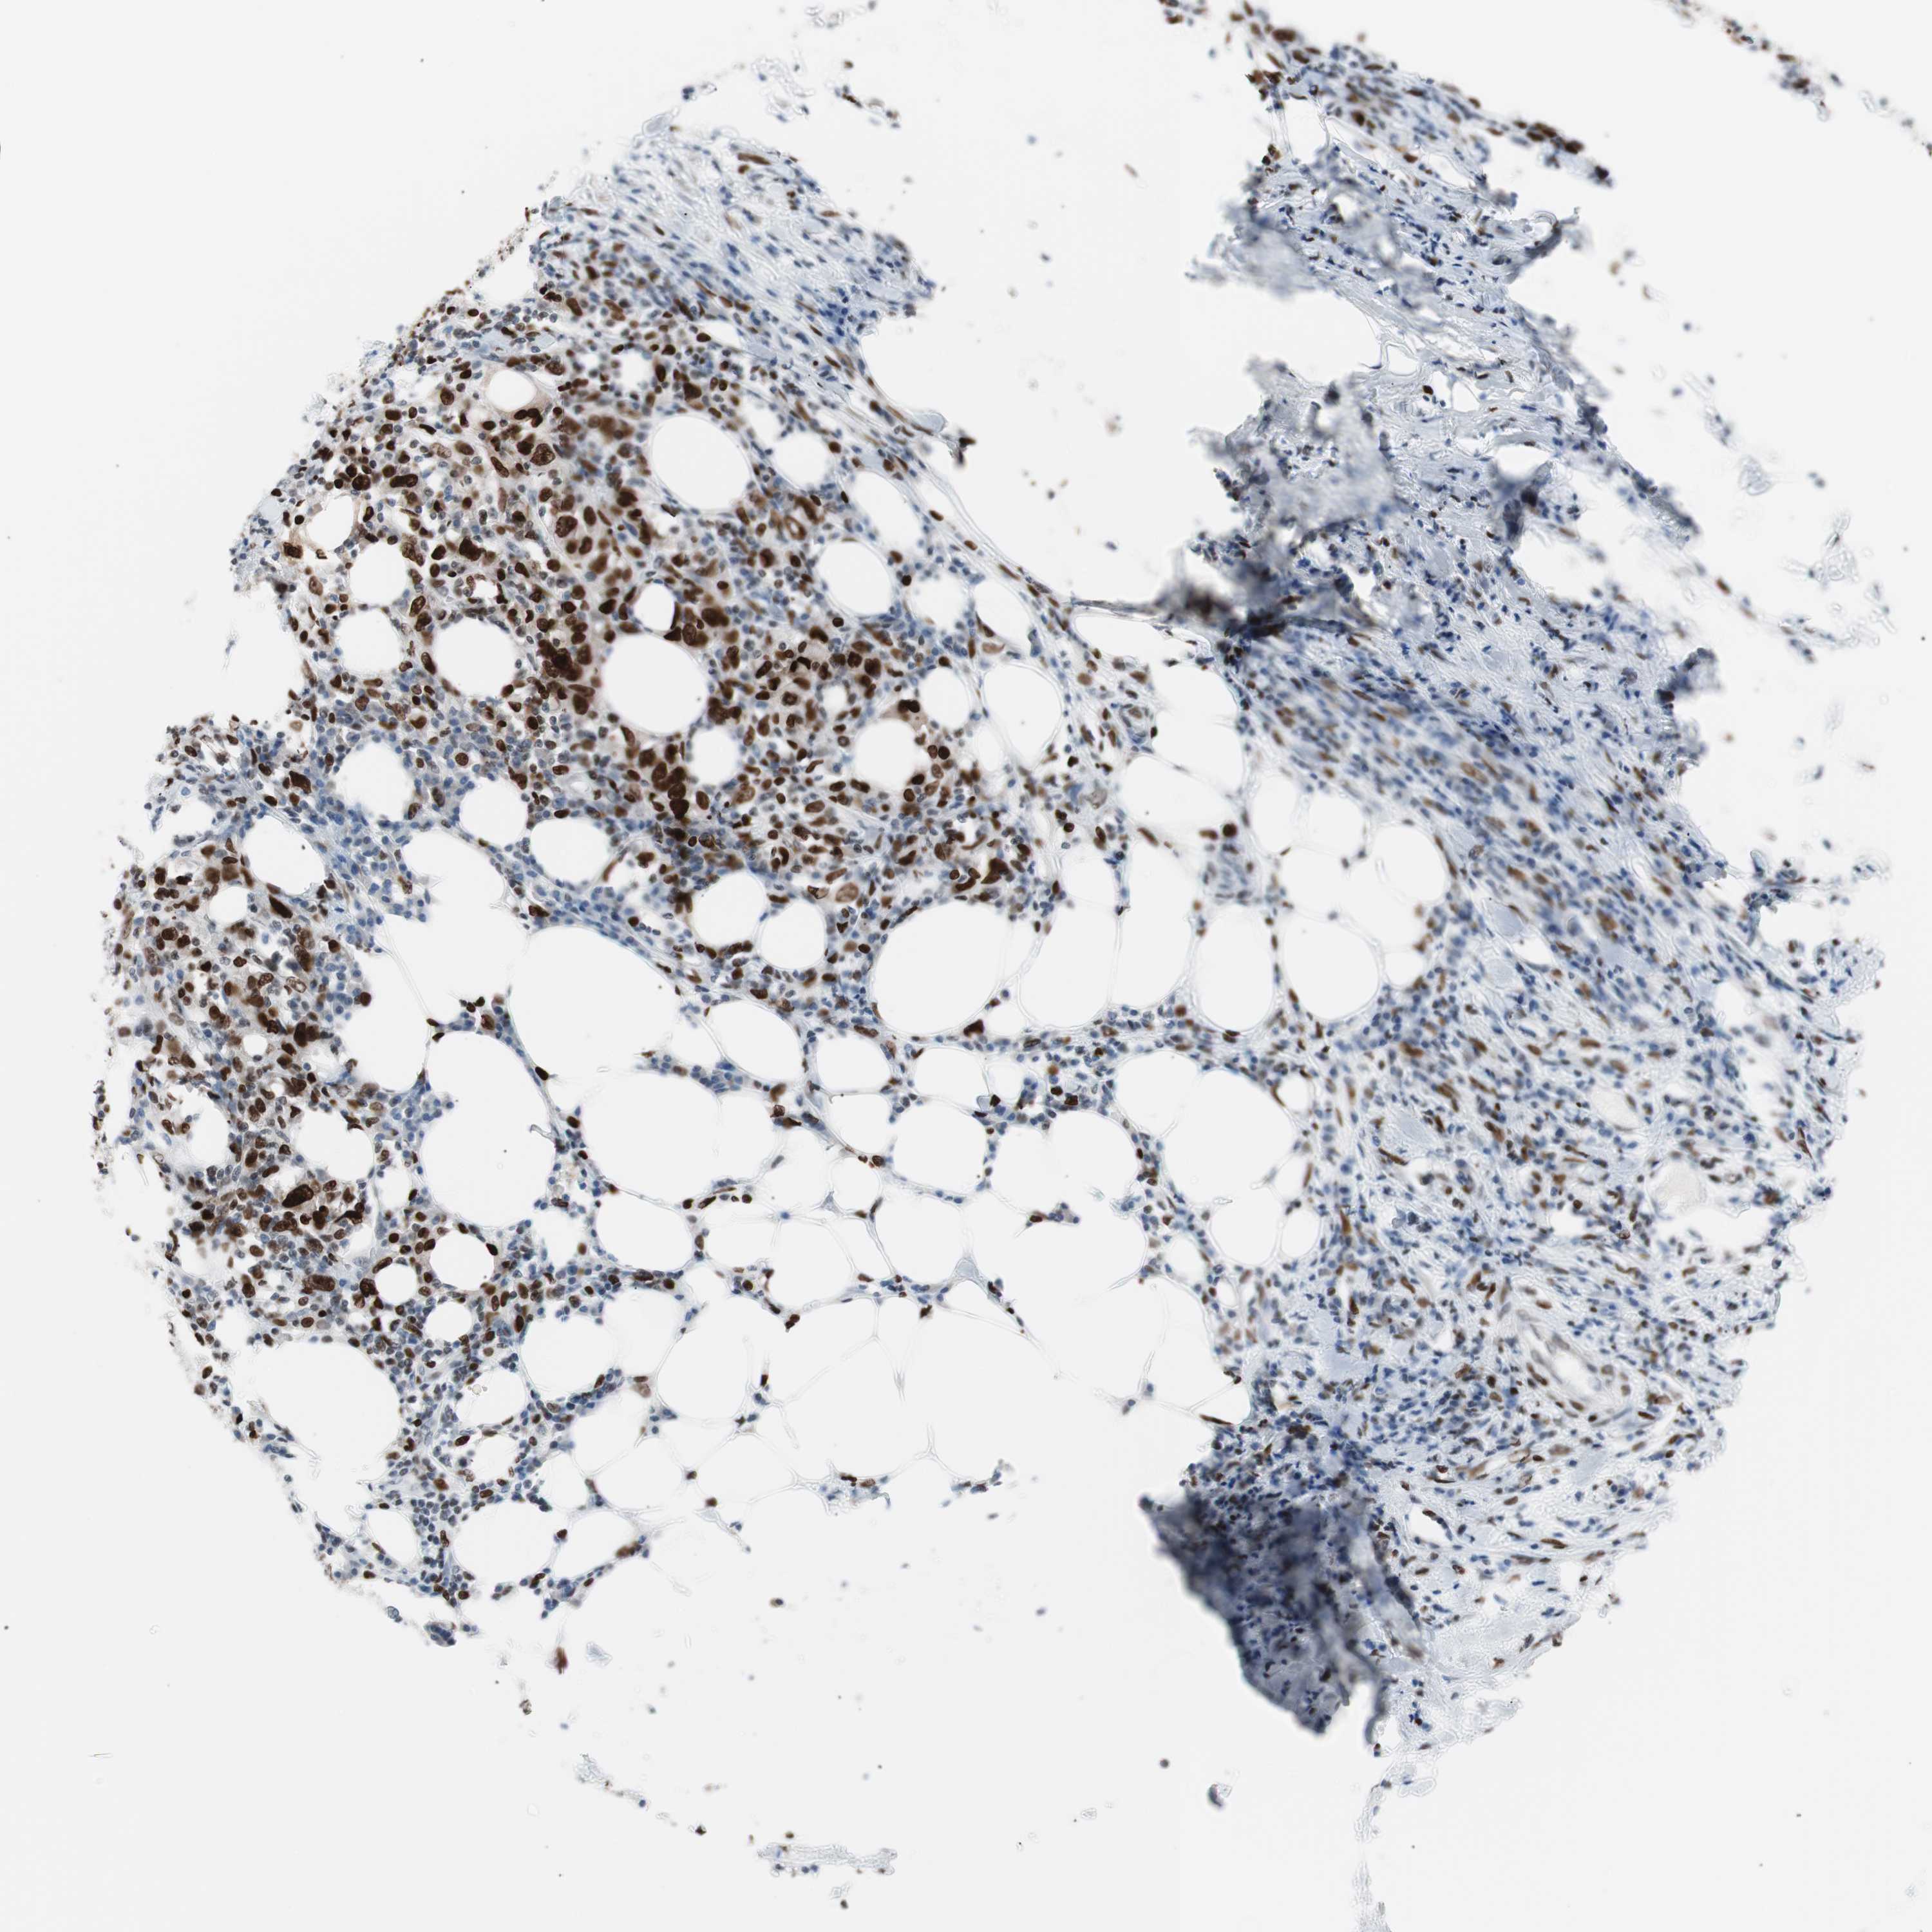

UROTHELIAL CANCER - Protein expressioni

A mouse-over function shows sample information and annotation data. Click on an image to view it in a full screen mode. Samples can be filtered based on level of antibody staining by selecting one or several of the following categories: high, medium, low and not detected. The assay and annotation is described here.

Note that samples used for immunohistochemistry by the Human Protein Atlas do not correspond to samples in the TCGA dataset.

Antibody stainingi

Antibody staining in the annotated cell types in the current human tissue is reported as not detected, low, medium, or high, based on conventional immunohistochemistry profiling in selected tissues. This score is based on the combination of the staining intensity and fraction of stained cells.

Each image is clickable and will lead to virtual microscopy that enables deeper exploration of all samples and also displays staining intensity scores, fraction scores and subcellular localization as well as patient and tissue information for each sample.

Antibody CAB004213

Staining

Medium

Moderate

>75%

Location

Urothelial carcinoma, Low grade

Urothelial carcinoma, High grade